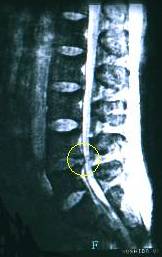

腰痛でヘルニアと診断された患者さんがMRIの写真を持って来院されました。

MRI写真の丸を見てください、左から何か飛び出しているのが見られます。

一つ上の正常な状態と見比べるとよくわかるります。

この写真で見る限り腰の骨5-4間がヘルニアしています。